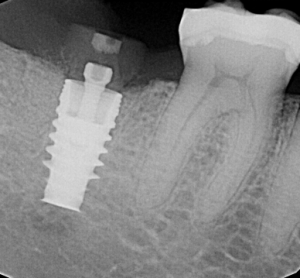

Preoperative 3D imaging is helpful in visualizing the patient’s anatomy and screening the ideal candidate. Since there is limited bone available, a dental implant with aggressive threading is important to obtain good primary stability. Typically, the socket is larger than the diameter of the dental implant and a bone graft is required to fill the space. A large stock, or customized healing abutment, can then be used to contain the bone graft and allow for ideal soft tissue healing.

Immediate implant placement in extraction sockets is a predictable procedure with favorable results. Immediate placement provides a tremendous benefit for patients as it eliminates the need for a second surgery and significantly reduces treatment time. With immediate placement patients can receive their new implant restoration four months after extraction, compared to the traditional eight month waiting period with two or more surgeries.